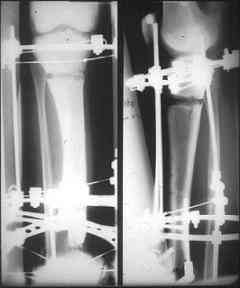

отделяемое. #1;#2. Стержневой апп. снят, наложен апп. Илизарова, дренажно-ирригационная система промывки раны. #3; #4. После стихания инфекции,

аппаратом постепенно создана рекурвация для сближения контактов мышц (сухожилий) передней группы голени. #5;#6. Наложен шов на сухожлилия М.

Tibialis anterior и M extensor digitorum L. Одновременно компактотомия костей голени в В/3 для замешение дефекта костей. #7;#8. Постепенно

исправлена ось и возмещен дефект. В результате восстановление тыльной флекcии стопы и функции конечности. #9;#10;#11